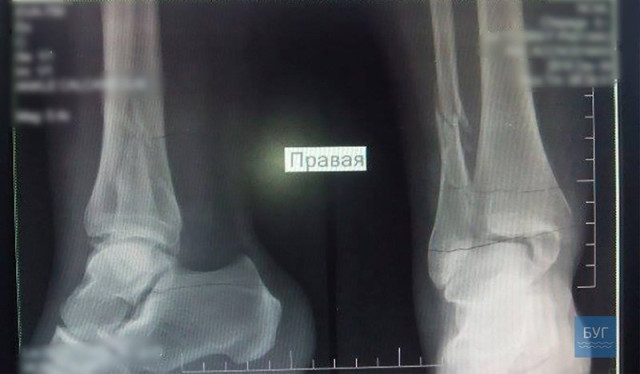

В травматологічному відділенні жінці встановили діагноз: перелом кісточок правої гомілки зі зміщенням.У одній палаті з Світланою Чепего на лікарняному ліжку – бабця, якій 81 рік. Крім поламаної ноги, розповідає, дошкуляє і травмована під час падіння рука. Причина травматизму та ж.